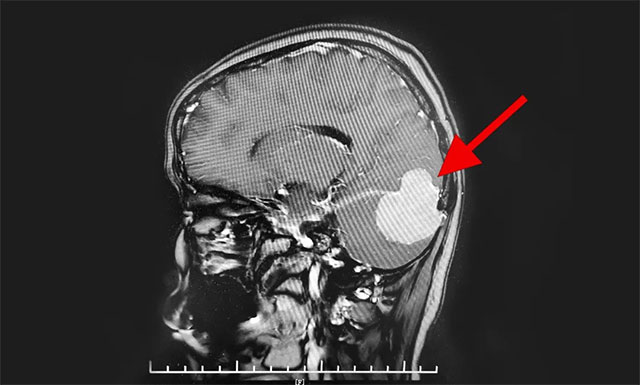

头颅MR增强显示,患者右侧后颅窝可见团块状异常信号病灶,大小近5公分,边缘清晰,轮廓不规整,向上凸入枕部,毗邻右侧小脑半球及枕叶受推压(右侧小脑少许水肿),右侧横窦明显受压,右侧枕骨受压变扁。

由神经外科6B病区主任潘仁龙、李士其教授、吴治群博士组成的专家组会诊后指出,患者颅内占位明确,根据影像学表现考虑为小脑幕脑膜瘤,并且肿瘤横跨小脑幕幕上幕下,十分罕见。肿瘤瘤体向上下两方向发展,大部位于后颅窝,瘤体已较大,不及时手术,会出现慢性枕骨大孔疝的急性发作,导致生命危险,患者手术指征明确。

▲ 脑膜瘤横跨小脑幕幕上幕下,十分罕见